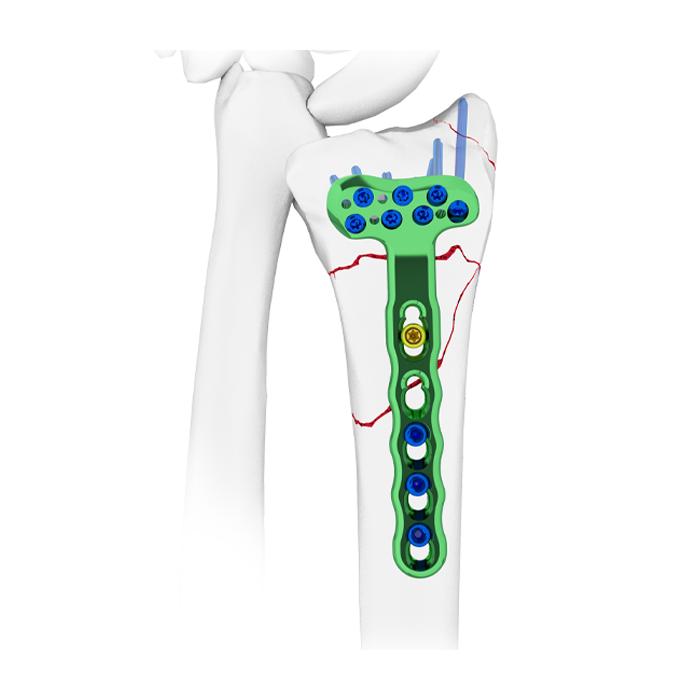

SISTEMA DE ARTROPLASTIA ANATOMICA DE LIGAMENTOS DEL PULGAR (ATLAS)

La técnica ATLAS está destinada a corregir la inestabilidad CMC del pulgar y facilitar un rápido retorno a la función mediante la colocación de fijaciones estables de anclaje basado en suturas en los sitios anatómicos de inserción del ligamento basal del pulgar.